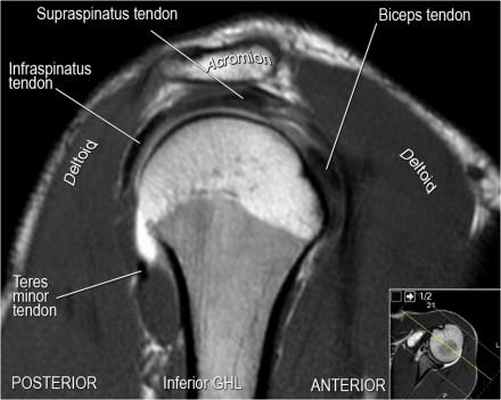

Изображение задних отделов плечевого сустава.

Отображены надостная, подостная и малая круглая мышцы и их сухожилия. Все они прикрепляются к большому бугорку плечевой кости. Сухожилия и мышцы манжеты вращателей участвуют в стабилизации плечевого сустава во время движения. Без манжеты вращателей головка плечевой кости частично сместилась бы из суставной впадины, уменьшив силу отведения дельтовидной мышцы (мышцы вращательной манжеты координирует усилия дельтовидной мышцы). Повреждение манжеты вращателей может привести к смещению головки плечевой кости кверху, в результате вызвая высокое стояние головки плечевой кости.